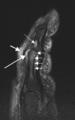

(a) T1-weighted and (b) short tau inversion recovery (STIR) magnetic resonance images of lumbar and lower thoracic spine in psoriatic arthritis. Signs of active inflammation are seen at several levels (arrows). In particular, anterior spondylitis is seen at level L1/L2 and an inflammatory Andersson lesion at the upper vertebral endplate of L3.